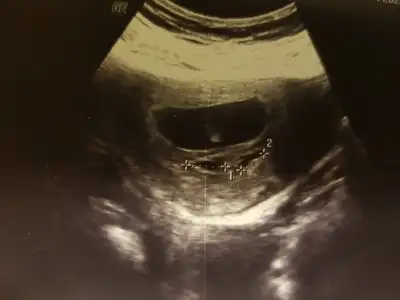

Canim bana da bir yorum yaparsan mutlu olurum sorum biraz zor sanki sag mı sol mu nerde belirsiz benim bebe

Havalianne__ Havalianne__ bak bi de böyle enterans bi pozu var burda yuvarlak gibi uzaktan bildiğin fasulye